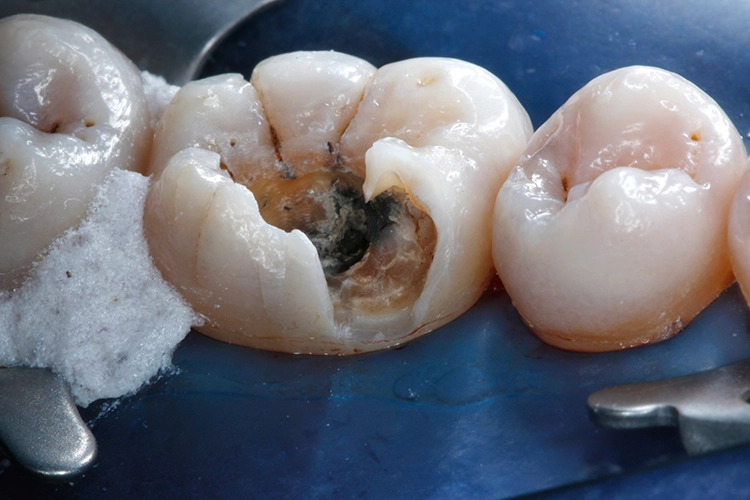

Ein 38-jähriger Patient erschien in unserer Sprechstunde mit einem frakturierten mesiolingualen Höcker neben einer okklusalen Amalgamfüllung am unteren rechten 1. Molaren (Zahn 46). Der Vorfall hatte sich bereits vor einer Woche ereignet, der Zahn war noch am selben Tag im zahnärztlichen Notdienst provisorisch mit einer Glasionomerzementfüllung versorgt worden (Abb. 1). Der Defekt erstreckte sich bis auf Höhe der marginalen Gingiva (Abb. 2).